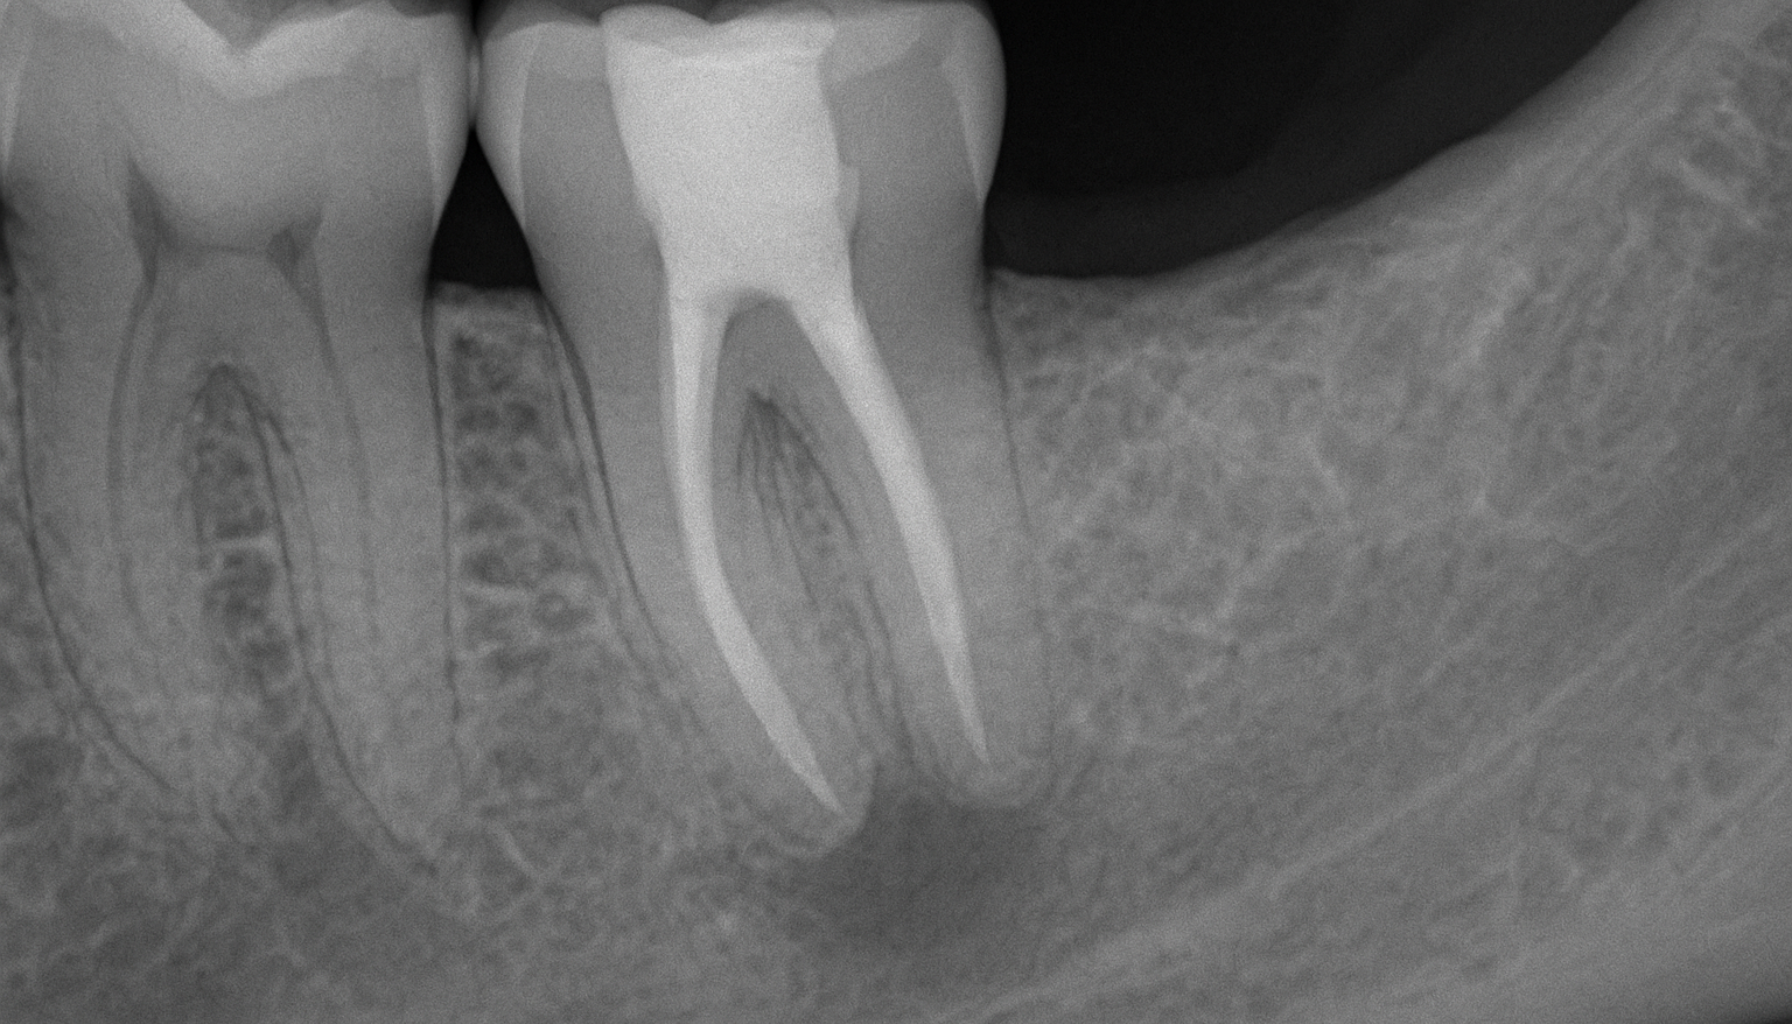

Rotfylle en tann innebærer fjerning av tannens pulpa (nervesystem) og rengjøring av rotkanalene ved hull i tennene og andre skader. Dette gjøres vanligvis med bedøvelse og behøver ikke å føles vondt ut. Tannen rotfylles etter rengjøring og desinfisering med et materiale for å forhindre bakterieinfeksjoner og bevare tannen.

Våre tannleger gjør denne behandlingen med lupebriller og bruker tiden som kreves for å få bort den infiserte nerven. Rotfylling innebærer at pulpa renses grundig for å fjerne bakterier og infisert materiale.

Ved neste avtale (3-4 uker etter første) fjernes den midlertidige fyllingen og rotkanalen vaskes og renses før det legges en permanent fylling i kanalen. Under rotkanalbehandlingen renses bort pulpa for å sikre at alle bakterier fjernes.

Det er viktig at tannen har vært helt symptomfri før man gjør dette andre steget av rotfyllingen. En permanent fylling legges på toppen, og dersom det er en tann lenger bak i munnen anbefales det en tannkrone.